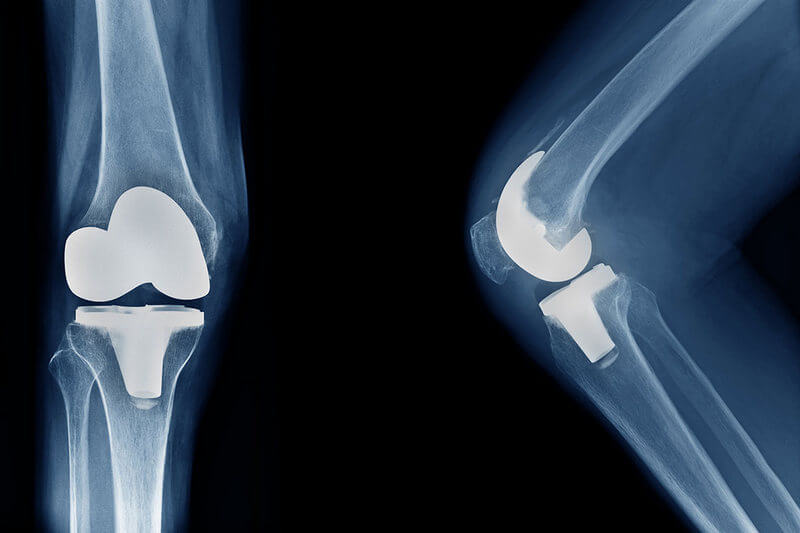

Εικόνα 3: Ολική αρθροπλαστική γόνατος

Υπάρχουν τέσσερα βασικά βήματα για τη χειρουργική επέμβαση αντικατάστασης του γόνατος που μπορεί να ονομαστεί με μεγαλύτερη ακρίβεια ως αρθροπλαστική επιφανειών του γόνατος επειδή αντικαθίσταται μόνο η επιφάνεια των οστών:

Προετοιμασία των οστών: Οι κατεστραμμένες επιφάνειες του χόνδρου στα άκρα του μηριαίου οστού και της κνήμης αφαιρούνται μαζί με μια μικρή ποσότητα υποκείμενου οστού.

Τοποθέτηση των μεταλλικών εμφυτευμάτων: Ο αφαιρεθείς χόνδρος και το οστό αντικαθίστανται από μεταλλικά μέρη που αναδημιουργούν την επιφάνεια της άρθρωσης.

Τα μεταλλικά εμφυτεύματα είναι κατασκευασμένα από κράματα μετάλλων (ατσάλι, τιτάνιο, κοβάλτιο) με επικρατέστερο υλικό το τιτάνιο. Είναι βιοσυμβατά καθώς και συμβατά με μαγνητική τομογραφία, μη τοξικά και χαρακτηρίζονται από μεγάλη αντοχή στον χρόνο. Αυτά τα μεταλλικά μέρη μπορούν να ενσωματωθούν στο οστό είτε με ειδικό ορθοπαιδικό τσιμέντο είτε να ενσφηνωθούν (press fit).

Διαμόρφωση επιγονατίδας: Η κάτω επιφάνεια της επιγονατίδας κόβεται και αντικαθίσταται με πλαστικό εμφύτευμα. Ανάλογα με την περίπτωση, η επιγονατίδα δεν μπορεί να μην αντικατασταθεί αλλά να απονευρωθεί και να αναδιαμορφωθεί η αρθρική της επιφάνεια.

Εισαγωγή πλαστικού διαχωριστικού: Ανάμεσα στα μεταλλικά μέρη εισάγεται το πλαστικό μέρος της τεχνητής πρόθεσης ονομάζεται πολυαιθυλένιο και ουσιαστικά υποκαθιστά τα μαλακά ενδαρθρικά στοιχεία της άρθρωσης (χόνδρο και μηνίσκους) για να δημιουργήσει μια ομαλή επιφάνεια ολίσθησης. Στα σύγχρονα πολυαιθυλένια που χρησιμοποιούμε, τα μόρια τους περιέχουν ισχυρούς σταυροειδείς δεσμούς (highly cross-linked), που προσφέρουν πολύ μειωμένους συντελεστές τριβής και πολύ μεγάλη αντοχή στο χρόνο.